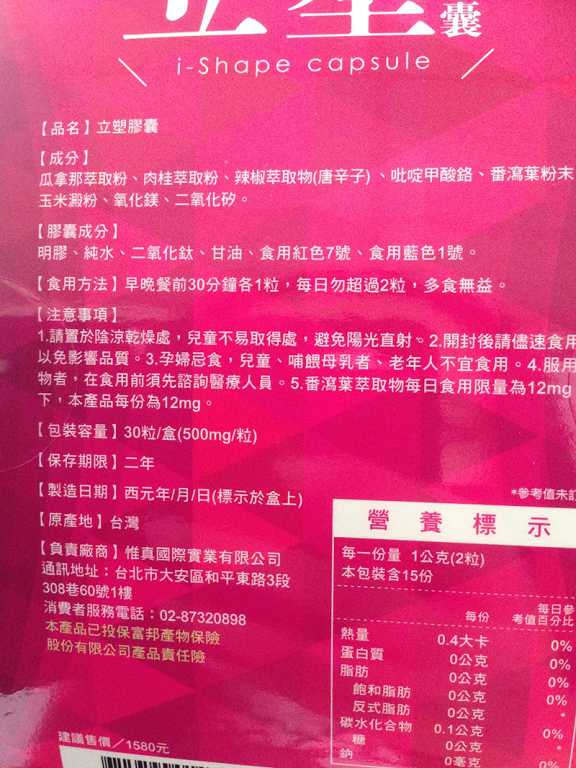

Supercut塑魔纖立塑膠囊的成分有:瓜拿那萃取粉、肉桂萃取粉、辣椒萃取物(唐辛子)、吡啶甲酸鉻、番瀉葉粉末、玉米澱粉、氧化鎂、二氧化矽。

之前上過相關課程,成分表是依照每項成分的多寡來排列順序,排在最前面的就是產品的主要成分!

食用方式:早晚餐前30分鐘各1粒,每日不超過2粒。(多食無益)

番瀉葉萃取物每日食用限量為12mg以下,

番瀉葉萃取物每日食用限量為12mg以下,